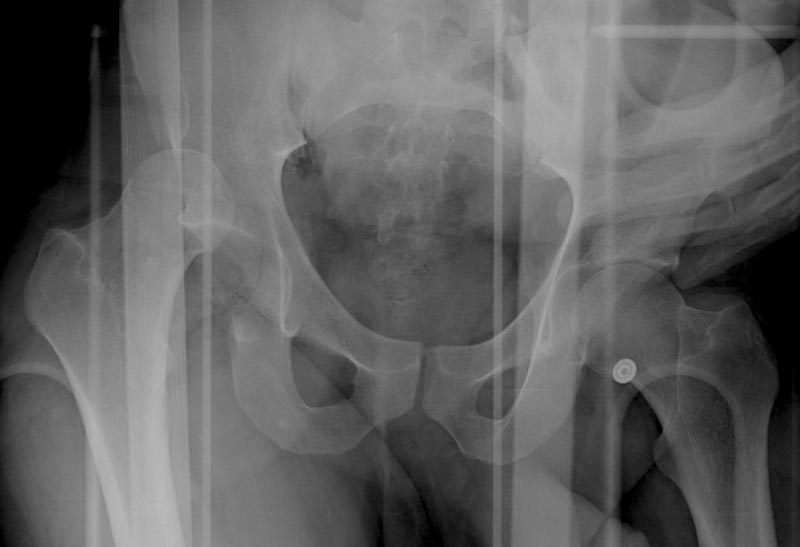

Выставлена на обсуждение (только одна проекция) рентгенограмма больного 25 лет, поступившего в приемное отделение, молодой дежурный врач сомневается в тактике лечения и спрашивает совета.

С его слов, больной стабилен, травму получил в результате автоаварии. Подскажите, что делать? Джолдас Кульджанов